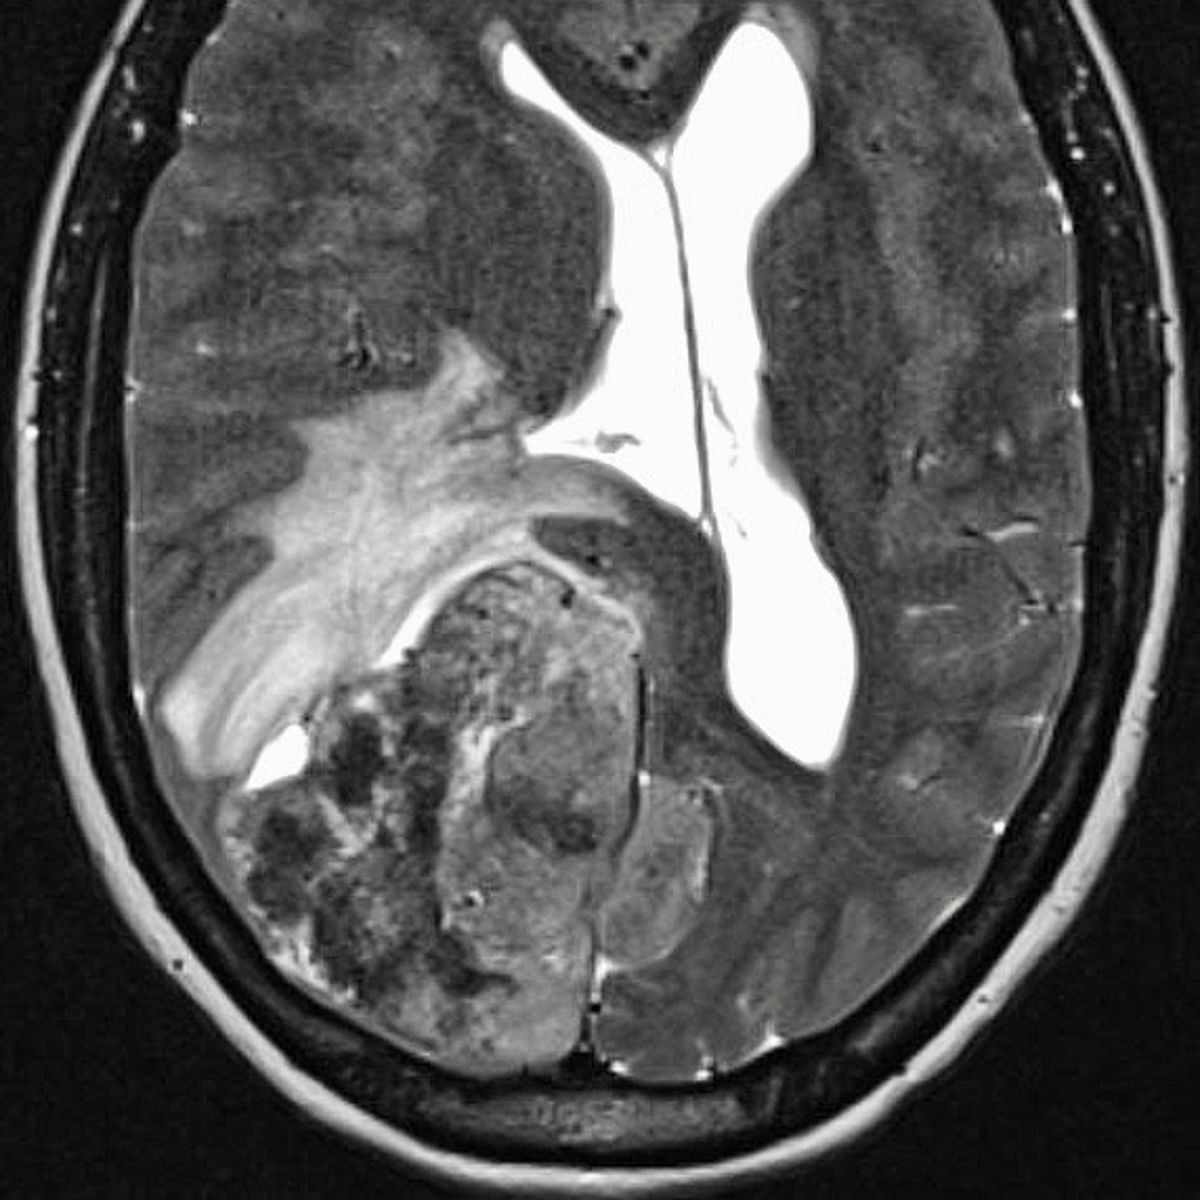

Gefäßmissbildungen und -tumore können zu Blutungen führen, aufgrund ihrer Größe lokale Probleme verursachen oder auch nur rein ästhetisch störend sein.

Die Neuroradiologie ist bei der Diagnostik solcher Gefäßveränderungen mit Computertomographie, Kernspintomographie und vor allem der Angiographie gefragt.

Im Rahmen der interventionellen Therapie sind endovaskuläre und perkutane Injektionen mit verödenden Substanzen, Gewebe- und Gefäßkleber möglich.